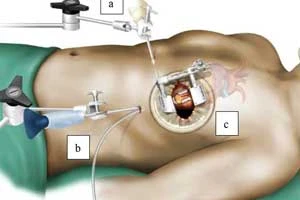

Keyhole / Minimally Invasive Heart Surgery

Small incision surgery with faster recovery

Keyhole / Minimally Invasive Heart Surgery

Small incision surgery with faster recovery